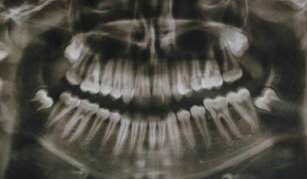

Моей дочери 26 лет. В детстве ударилась, затем примитивная шапочка с корсажной лентой на зуб, когда прорезался постоянный, в настоящее время — результат. В семье ни у кого патологии нет. Это дело случая и нажима корсажной ленты на зуб.

Можно ли исправить (к лучшему), хотя бы к лучшему, без вмешательства хирургии? Какое Ваше мнение? Есть ли необходимость что-то удалять?

Обратитесь на очный прием к врачу, без рентген снимков говорить о методах восстановления невозможно.